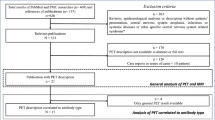

Our literature search and manual addition yielded 630 papers after duplicate removal. At the first step of screening, 489 studies were excluded and the remaining papers were further reviewed accurately and finally, 22 studies with a total of 332 participants were entered into our qualitative synthesis (Fig. 1).